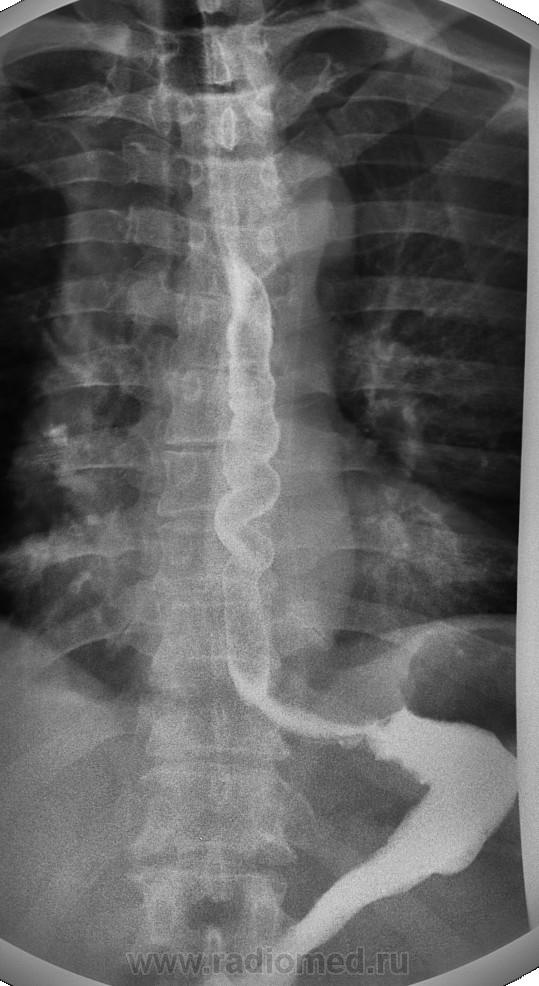

Просто красивые снимки

синдром Баршоня — Тешендорфа, он же чёткообразный или штопорообразный пищевод. Качество супер.

Однако, качество не то чтобы отличное: зерно для такого размера изображения очень крупное. Да и понятно почему. КРТ «Электрон» – это тот же флюорограф электроновский приделанный к телеуправляемому штативу корейскому либо итальянскому. Но главное – ЭОП, видимо собственного дизайна. Разрешение 1024х1024 точки для 16" маловато будет.

Уважаемый Петрович, Зерно  на данных снимках обусловлено применением фильтров, сцелью усиления контрастности. Для оценки зерна просьба посмотреть снимки "Ваше мнение?".  А аппарат  наверное один из лучших в своем классе.